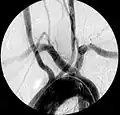

L'artère sous-clavière aberrante, ou artera lusoria, est une rare variante anatomique de l'origine de l'artère sous-clavière droite. Cette anomalie vasculaire congénitale est l'anomalie la plus courante de l'arc aortique[2], survenant chez environ 1 % des individus[2]. Au lieu de naître de la division du tronc artériel brachio-céphalique, l'artère sous-clavière droite naît alors directement de la crosse aortique. Elle possède un trajet rétro-œsophagien pouvant être source de dysphagie.

Artère sous-clavière aberrante au scanner axial. (1) trachée, (2) œsophage, (3) Artère sous-clavière aberrante.- Artère sous-clavière droite aberrante à l'angiographie.